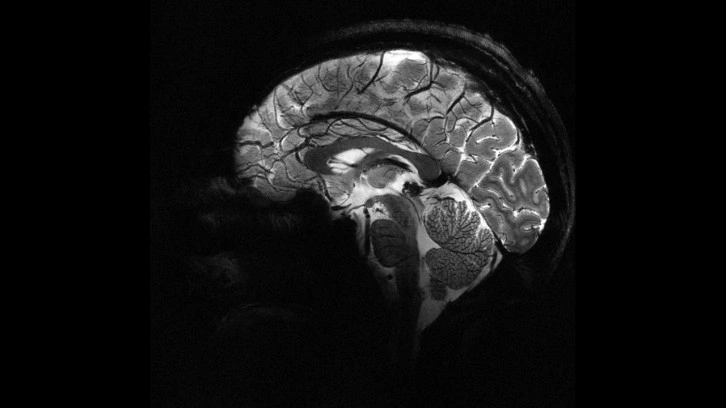

Fransa Atom Enerjisi ve Alternatif Enerjiler Kurumu (CEA), dünyanın en güçlü manyetik rezonans görüntüleme (MRI) cihazıyla elde edilen, insan beyninin en net görüntüsünü yayınladı.

CEA'dan yapılan yazılı açıklamada “Iseult” adlı MRI cihazıyla çekilen beyin görüntüsünün 20 yıldan uzun süren bir çalışma sonucu elde edildiği belirtildi.

Yapılan çalışmalar kapsamında MRI cihazının son birkaç ay içerisinde yaklaşık 20 sağlıklı gönüllü üzerinde test edildiği kaydedilen açıklamada, neredeyse 4 dakikada en net beyin görüntüsünün elde edildiği aktarıldı.

Açıklamada, 11,7 Tesla manyetik güce sahip Iseult MRI makinesiyle kısa sürede çekilen görüntülerin, hastanelerde yaygın kullanılan cihazlarla elde edilmesinin saatler sürebileceği kaydedildi.